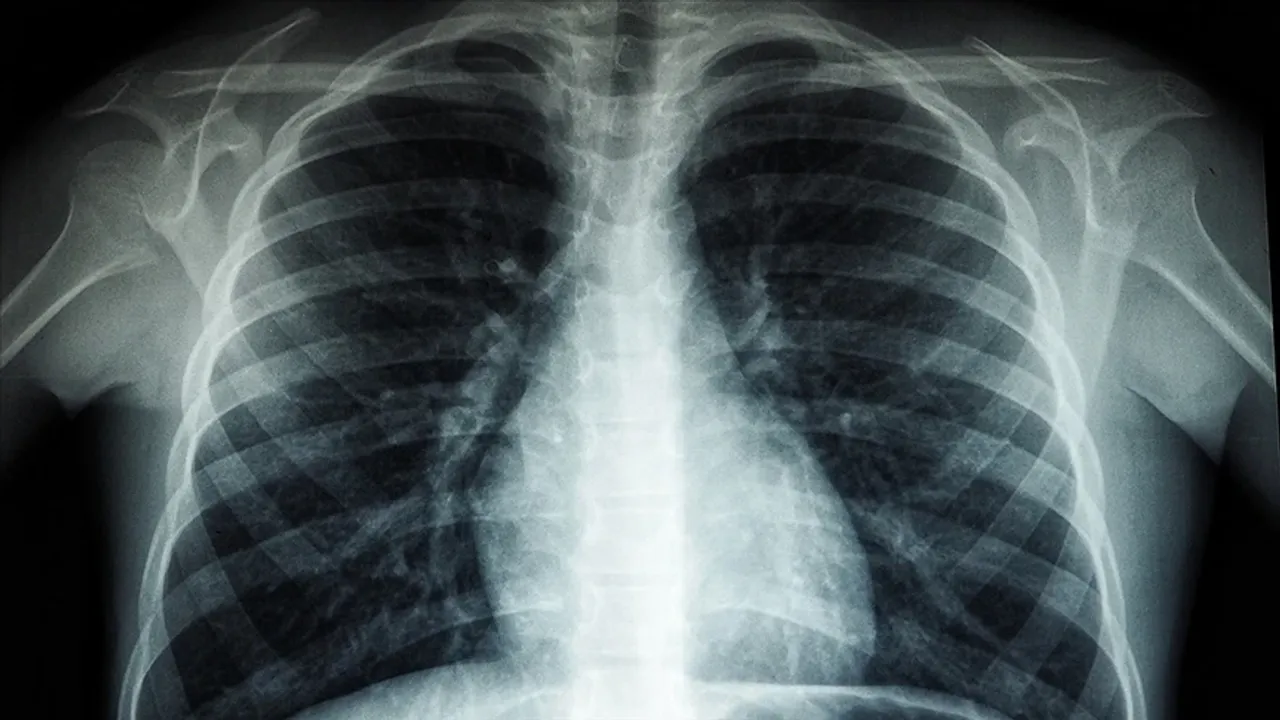

ERKEN TANININ ÖNEMİ VE BELİRTİLER

40 yaş üstü ve sigara içen kişilerin düzenli kontrolleri hayati önem taşıyor. 50 yaş üstü sigara kullanıcıları için yıllık düşük doz akciğer tomografisi öneriliyor. Önemli uyarı belirtileri şunlardır: